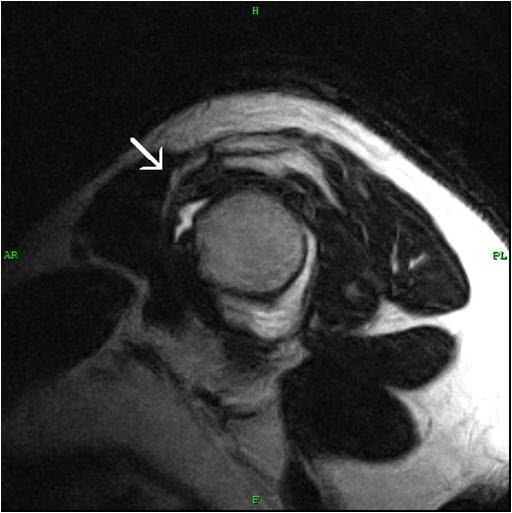

Pulley LesionShoulder MRI Sumer's Radiology Blog Pulley Injury Radiology multiple sequential pulley injuries result in tendon bowstringing, which decreases tendon excursion and prevents full digital. images were assessed by two experienced radiologists for the presence of pulley rupture. our review identified 22 studies investigating a2 pulley injuries with us (15 studies), mri (9 studies), or ct (2 studies),. a thickened first annular pulley may lead. Pulley Injury Radiology.